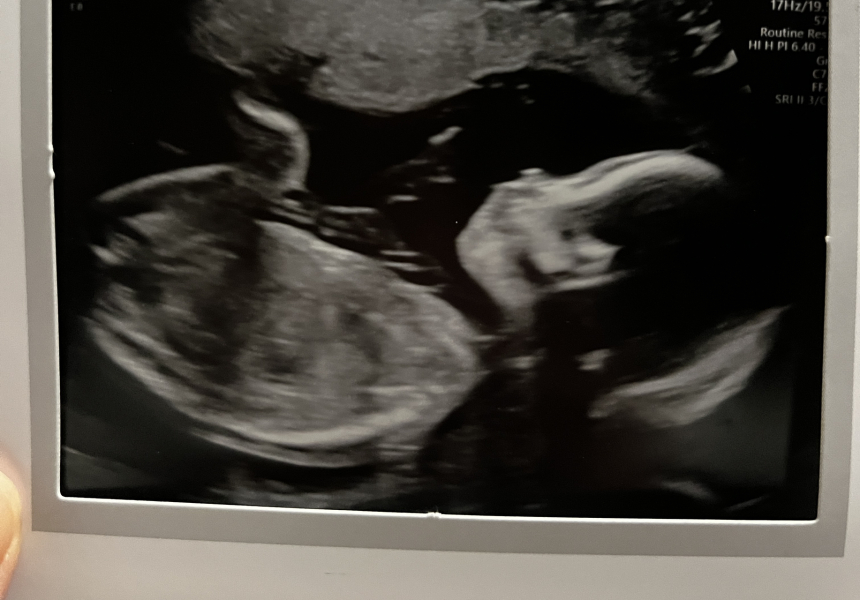

@TheBirdintheCave scan was this morning all looked good no issues to report thank goodness 🥰 I held off the temptation to find out what we're having it was close though part of me really wanted to know. I can't believe they cancelled your scan and didn't tell you that's terrible 😳have they rebooked it?

@bringmearainbow Aww, look at that cute little face! Congratulations again :D They did rebook my scan for tomorrow (and are redoing all the others which will be a nightmare as I'll now have loads more bits of paper to file and dates to check through etc). Considering just cancelling everything and not bothering.

@bringmearainbow What a lovely surprise this little baby has been. Beautiful scan as well. I’m 2 weeks past mc and plant to try again straight away. I’m a bit nervous because it took us 17 cycles.